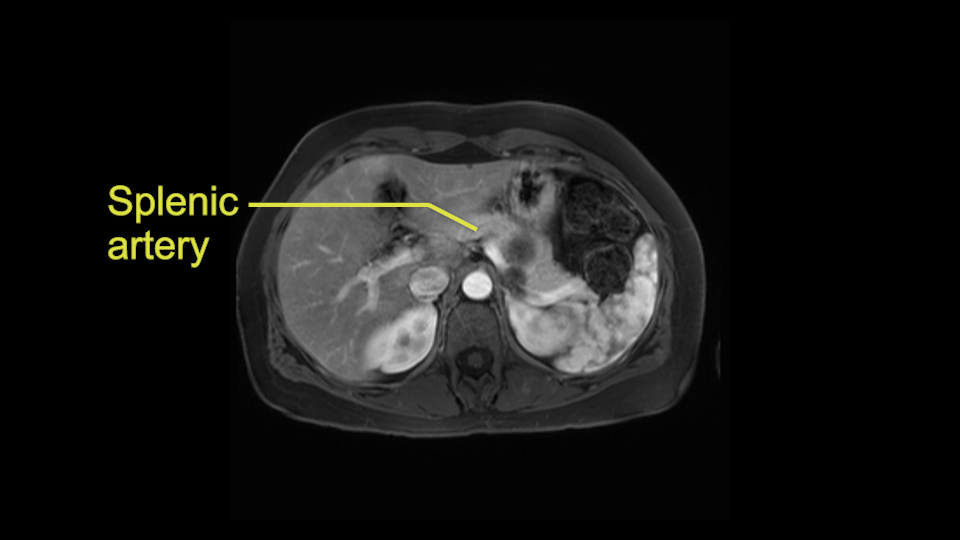

The second slowing down moment or consideration I give to a distal pancreatectomy is the anatomy of the portal vein and the splenic artery. And so I look here and the anatomy is pretty straightforward. The splenic vein comes off normally and runs behind the pancreas and I can see the artery superior to that, again coming off in a normal manner from the celiac axis. So those two things, the portal vein and the splenic artery will be taken normally in this procedure.

I think the splenic vein, once I have slowly teased it off from the cyst and from the retropancreatic parenchyma, I would put a vessel loop around it to serve as a traction. So once you have the vessel loop or probably umbilical tape, to retract or pull the pancreatic parenchyma while we slowly tease it off and try to move superiorly to be able to expose the splenic artery. That is again another slow-down moment because sometimes we think that it is the splenic artery at the superior edge of the pancreas, but it could also be the hepatic artery as it branches from the celiac artery.